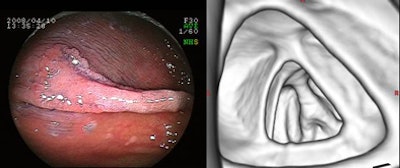

| The overall detection rate was only 56%, based on the combined detection rate of 70% for LSTGs and 25% for LSTNGs. There was a significant difference in detectability of the two types by Fisher's exact test (p = 0.014). Interestingly, lesion size was not a significant factor in detectability. |